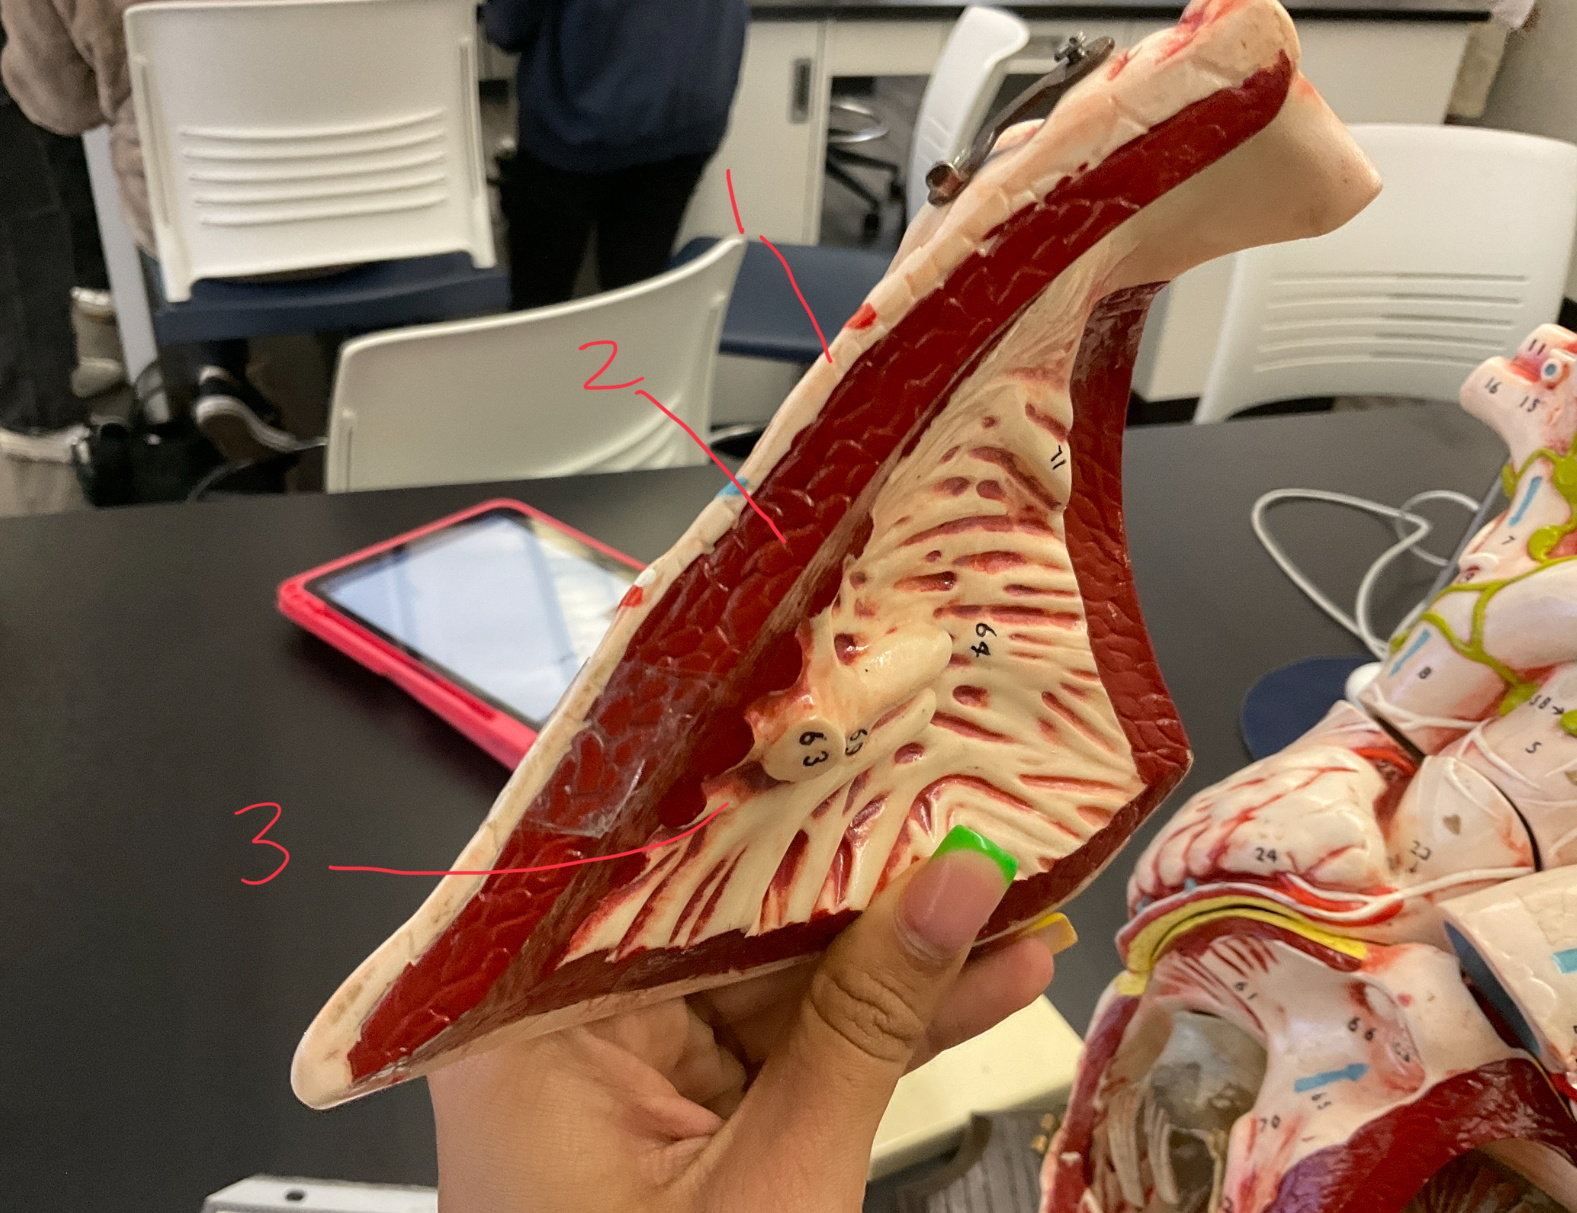

11 (not smooth part)

trubeculae carneae

1

papillary muscle

2

chordae tendineae